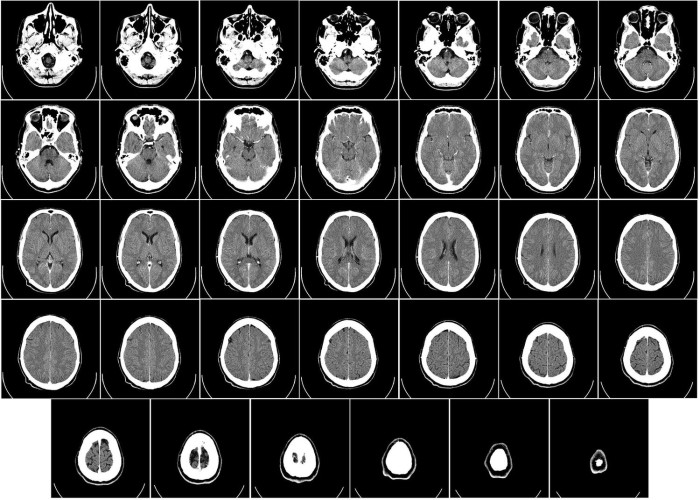

Un estudio firmado por Fidalgo y colaboradores utilizaron escáner para diagnosticar la presencia de Cephenemya en 30 corzos abatidos en Galicia y Castilla y León.

La prevalencia de la infestación fue del 40%, siendo mayor en machos (45%), que en las hembras (25%) y en todos los casos en los que se diagnosticó por escánder posteriormente se confirmó mediante la necropsia, lo que implica que esta técnica puede ser una alternativa eficaz para el diagnóstico y, aunque es verdad que no está al alcance de cualquiera, si puede tener una gran importancia para mejorar el conocimiento de esta enfermedad y contribuir a mejorar su gestión en las poblaciones afectadas, preservando en todo caso la integridad de los trofeos que puedan ser empleados en las investigaciones.